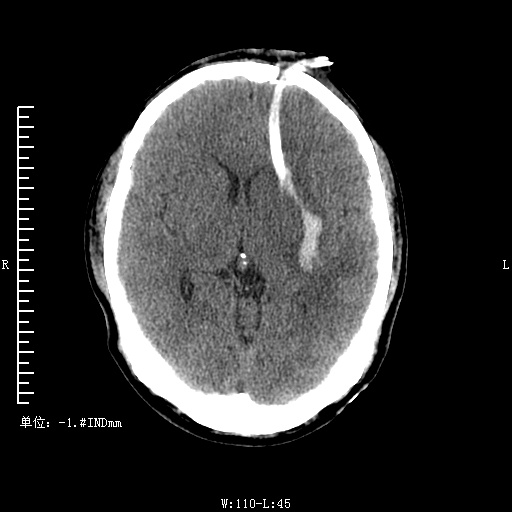

患者中年男性因"高处坠落伤后头昏,头痛5小时"急诊入院。查体:急性病容,表情痛苦,浅昏迷,检查不合作。GLASGOWS评分8分(E2V2M4),表情痛苦。右侧瞳孔2mm,左侧4mm,双侧瞳孔对光反射均迟钝,角膜正常,结膜无充血。外耳道无溢液。左侧鼻腔血渍。全身感觉存在。四肢肌力V级,无不自主运动。全身浅、深反射均正常。巴林斯奇征及克尼格征未引出。植物神经功能正常。全身多处软组织挫伤。左锁骨区骨擦感。头部CT示:左额颞部硬膜外血肿,中线偏移,蛛网膜下腔出血。入院后予以脱水,抗纤溶等治疗,积极完善术前相关检查,急诊全麻下行左额颞顶部硬膜外血肿清除术、左额颞顶硬膜下血肿清除术、左侧硬脑膜修补术、去骨瓣减压术,术后入ICU。经抢救治疗后患者苏醒,患者经治疗现患者神清,回答切题,头部伤口愈合可II/甲,未见溢液及溢血,复查颅脑ct恢复可,予痊愈出院。

下为去骨瓣术区: